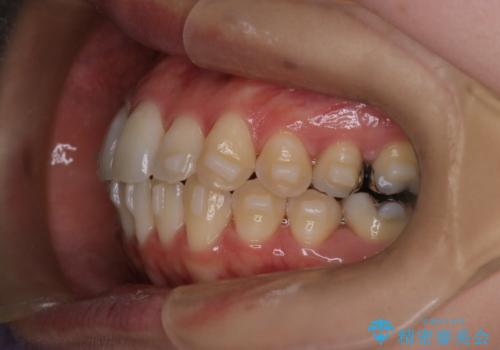

- 前歯のガタガタを主訴に来院された患者様です。

前歯の傾きも少し内側に入るように計画をたて、インビザラインにて治療を行いました。

このぐらいのガタガタであれば、インビザラインで簡単に治すことができます。